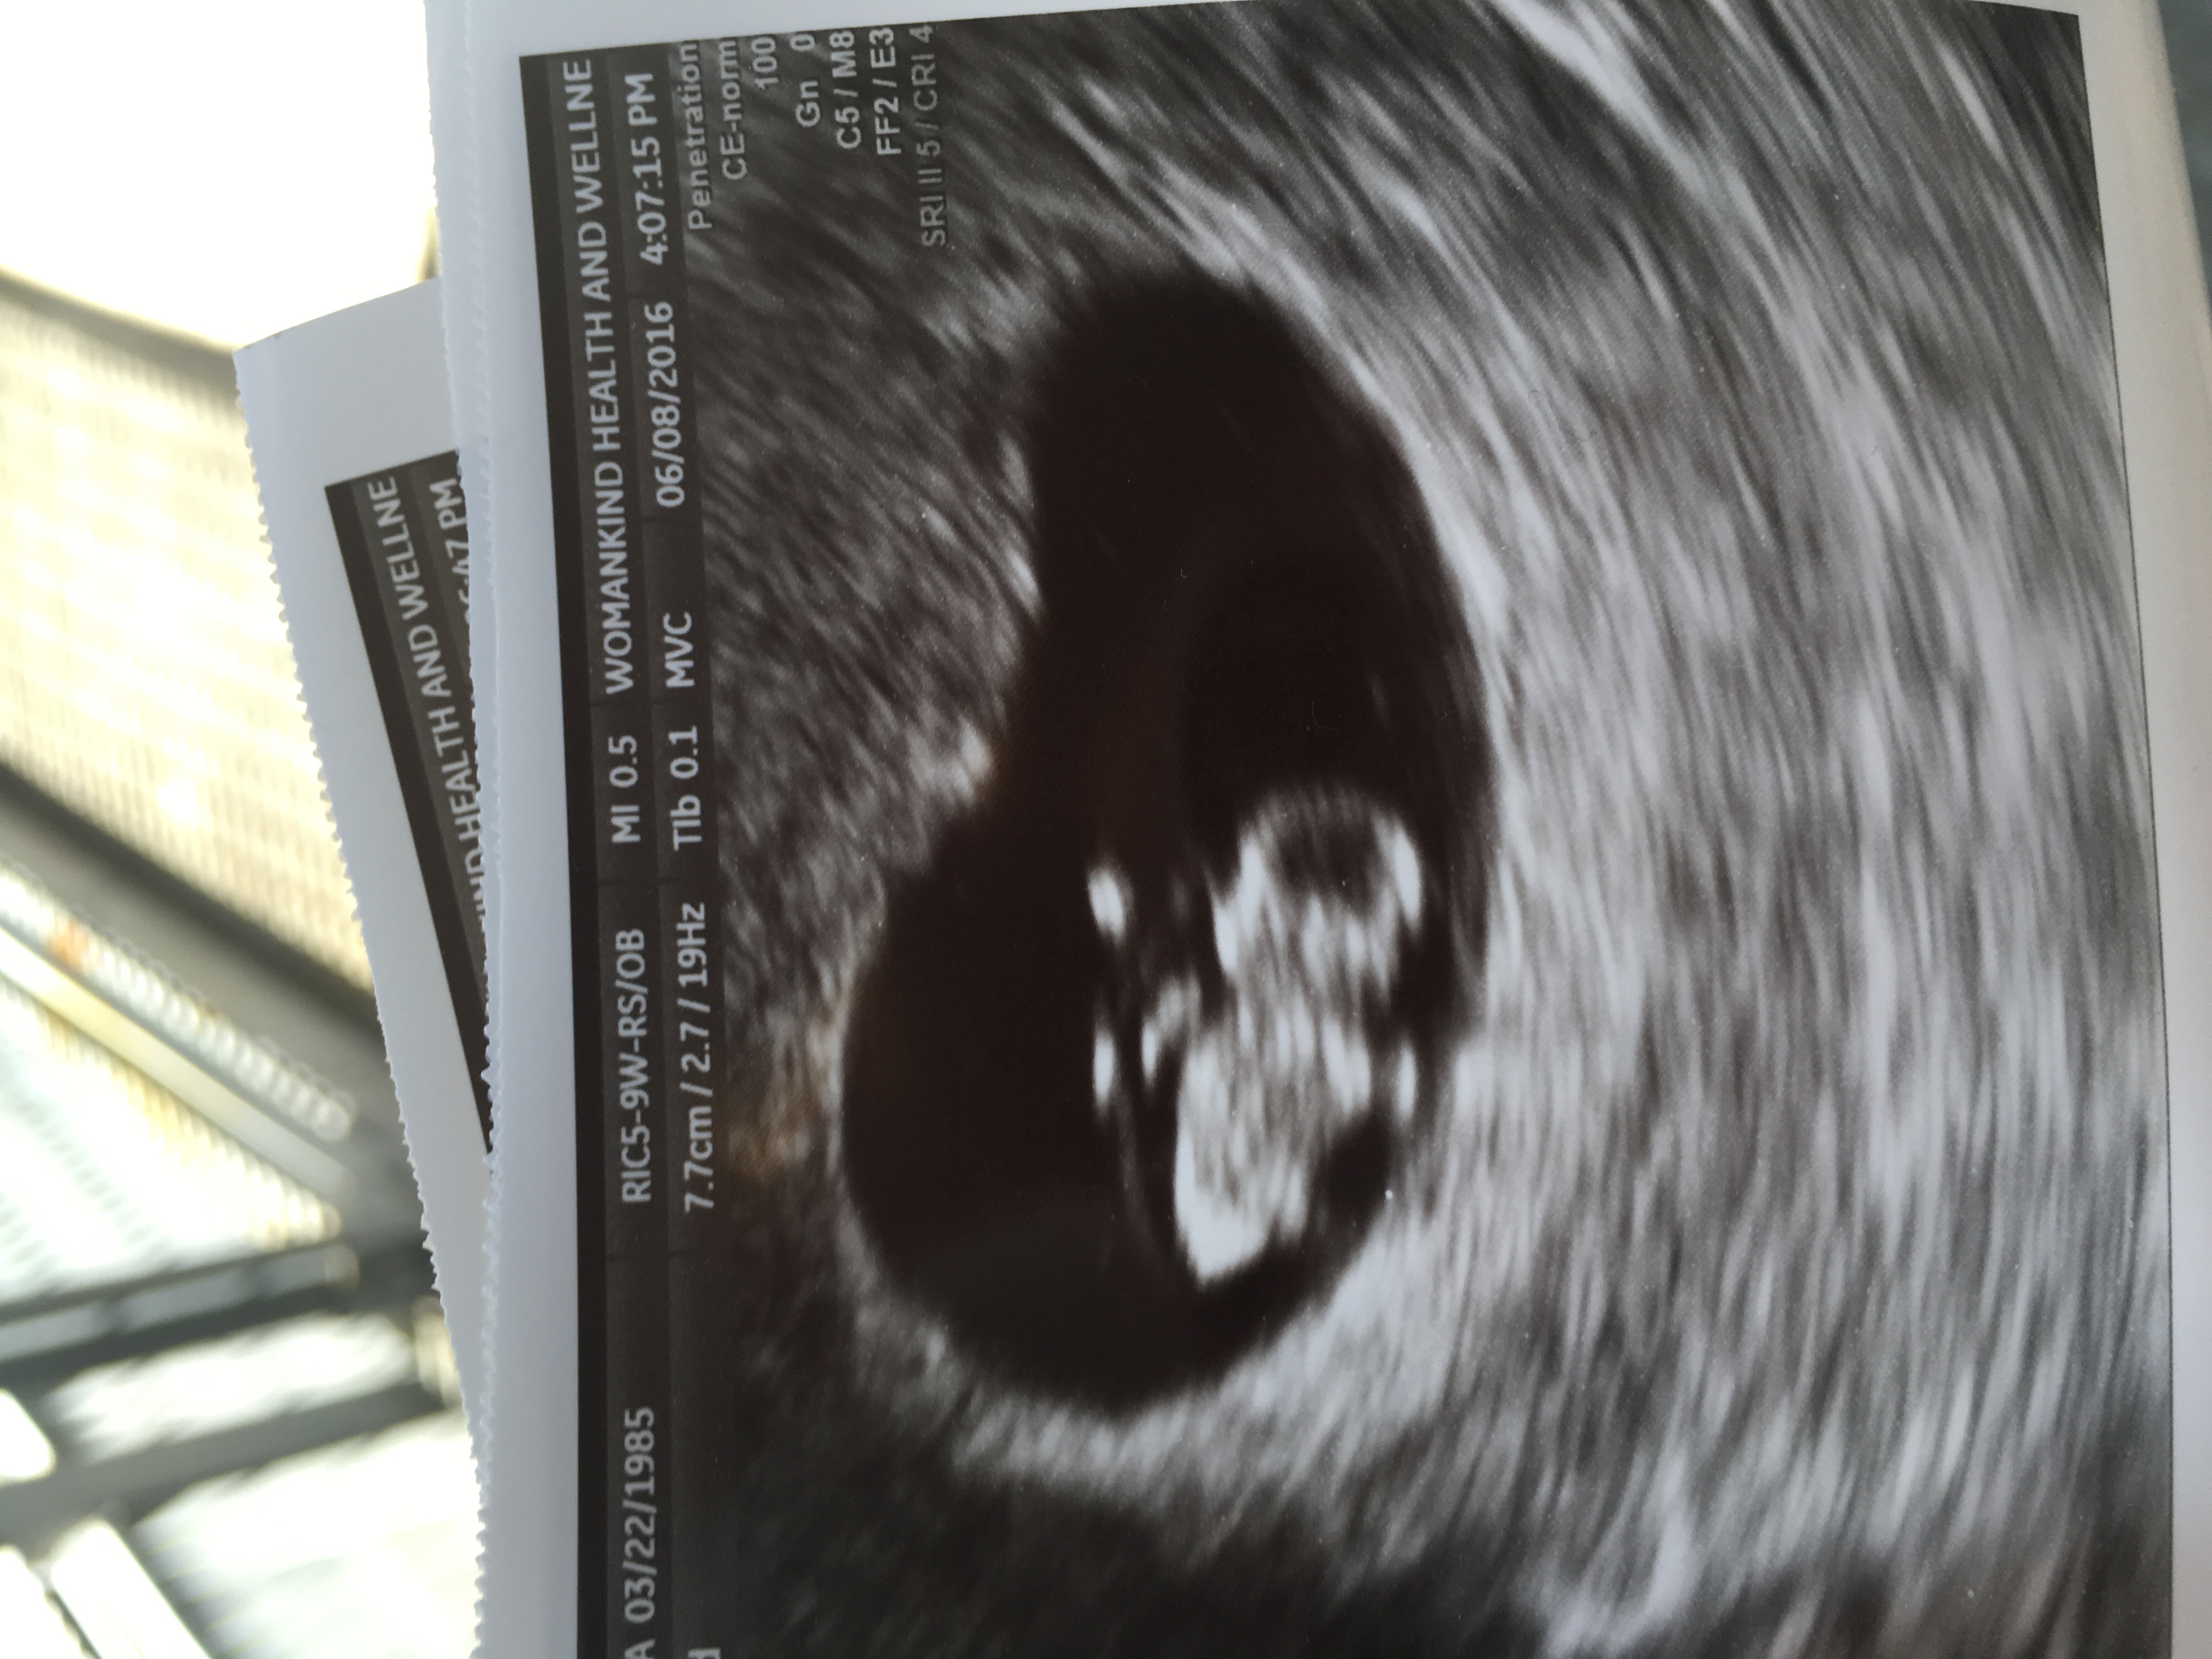

I had a transvaginal ultrasound today 8 weeks. Attachment 31659

No guess from me, but how beautiful is that sight?? :heart: